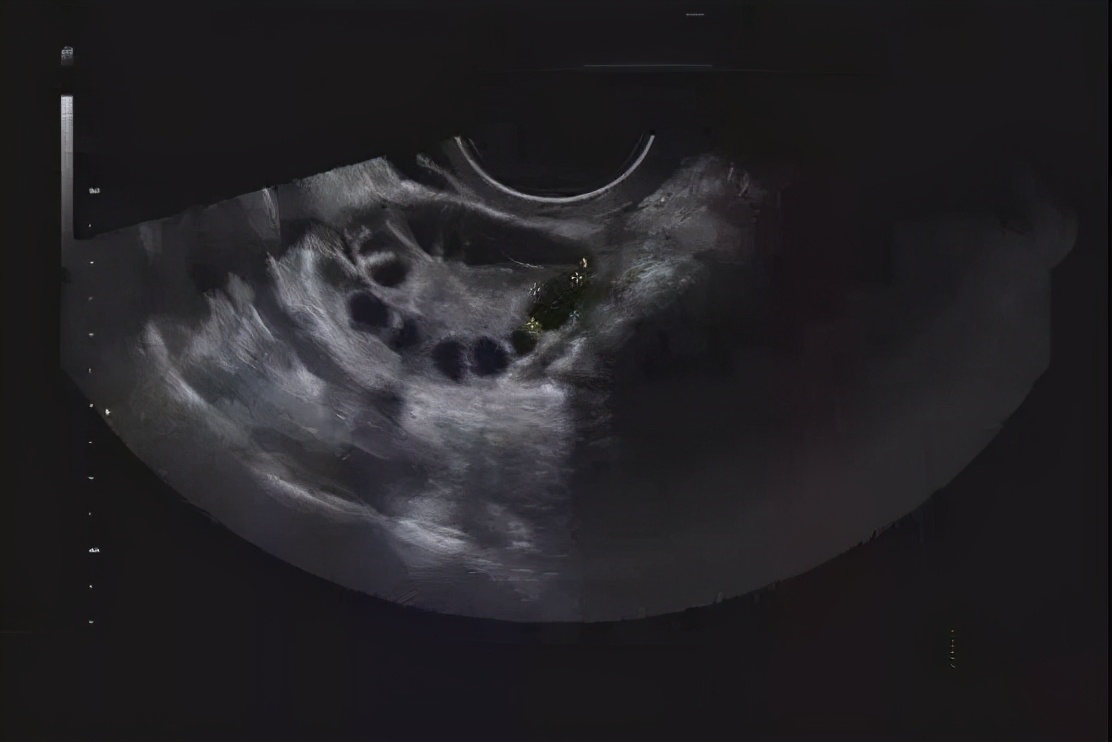

除了上面三种体征外,还有一个就是卵巢多囊样改变也即是多囊卵巢,是指卵巢体积增大,可以通过B超检查可以发现多个不成熟的直径2-9mm的卵泡 ≥12个,呈串珠状环绕在卵巢周围。但它和多囊卵巢综合征是不一样的,多囊卵巢是正常人、服用避孕药或者其他原因没有排卵的,是一种征象,而多囊卵巢综合征是一种疾病。

3、超声显示卵巢有多囊样改变。